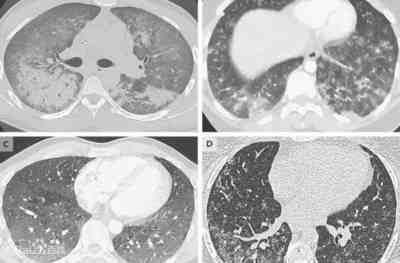

另外值得注意的是,曾有应对过武汉新冠疫情的权威专家,在查阅了60篇涉及美国“电子烟肺病”病例的研究论文,对其中142位电子烟肺病患者的250张肺部影像图片、临床信息以及文献原文进行了仔细全面的研究后,发现这些病例中有16个更有可能是新冠肺炎的“疑诊患者”,其中有5个临床症状和治疗情况相对完整的患者,被这些专家认定为“中度可疑”。而这16个病例中有12个病例的发病时间都在2020年以前。